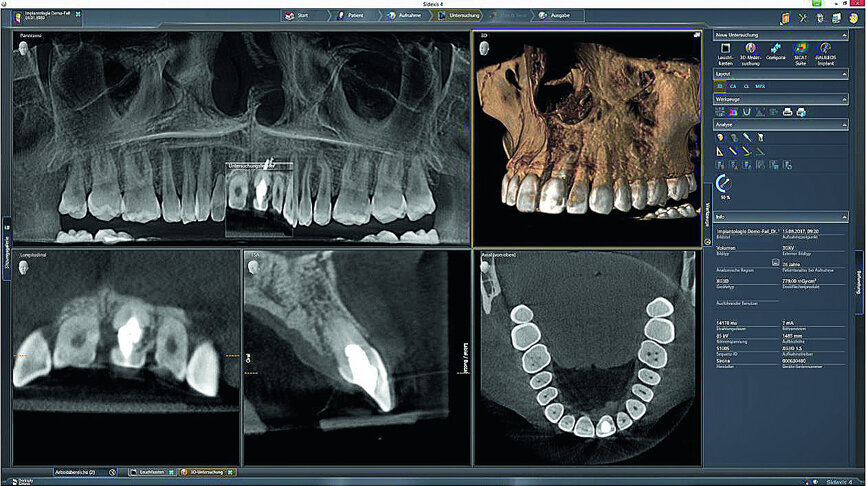

Fig. 3: The initial situation in 3-D in the Sidexis 4

imaging software (Dentsply Sirona) showed good apical bone substance with the possibility of immediate implantation.

The female patient, born in 1989, came to my practice with problems at tooth #21 caused by a childhood trauma. The gingival margins were reddened and bled when probed. The intraoral radiograph showed posttraumatic resorption of the root, and the tooth could therefore not be preserved (Figs. 1 & 2). The tooth was to be replaced by an implant with an all-ceramic crown immediately after extraction. To plan the procedure, a 3-D radiograph (Orthophos XG 3D, Dentsply Sirona) was taken. It was important to assess the available horizontal and vertical bone and evaluate apical osteolytic processes after the failure of endodontic treatment and in the region of the crestal bone due to progressive dentinal resorption. The integrity of the vestibular lamina was preserved, and there was sufficient apical bone to allow immediate implantation with immediate loading (Fig. 3).

After scanning the upper jaw, tooth #21 was deleted in CEREC to simulate the initial postoperative situation. The prosthetic proposal for tooth #21 was used to optimise implant planning and to produce the surgical guide (Figs. 4 & 5). In the implant planning software (Galileos Implant, Dentsply Sirona), the prosthetic proposal was superimposed over the CBCT data for the optimal positioning of the implant. In this way, sufficient vestibular distance was ensured, and the correct size of the implant for optimal primary stability could be selected (Fig. 6).

For this case, I used the digital workflow from Dentsply Sirona. After having tested different systems, it proved to be especially efficient and easy. The individual steps, from imaging and diagnosis using the scan, ordering the surgical guide and planning surgery up to producing the temporary restoration and the final prosthesis, are very well coordinated. The interface to SICAT is included in the planning software and enables one-click ordering. Even if I do not use a surgical guide for every implantation, I find it to be very useful depending on the indication.